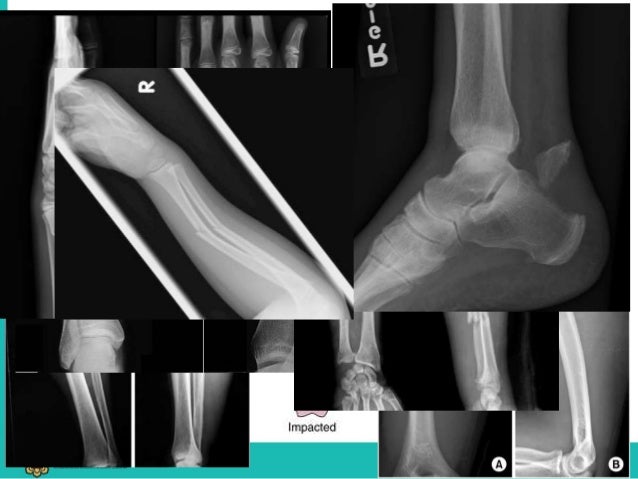

#COMMINUTED FRACTURE COMMON LOCATION SKIN#

This type of fracture is particularly serious because, once the skin is broken, infection in both the wound and the bone can occur. If the bone breaks in such a way that bone fragments stick out through the skin or a wound penetrates down to the broken bone, the fracture is called an "open" or compound fracture. The injury to surrounding soft tissues, such as muscle, tendons, nerves, and skin.The injury to the cartilage surfaces of both the acetabulum and the head of the femur.The amount each piece is out of place (displaced) - In some cases, the broken ends of bones line up adequately in more severe fractures, there may be a large gap between the broken pieces, or the fragments may overlap each other.The number and size of the fracture fragments.The severity of the injury depends on several factors, including: If the joint remains irregular or unstable, ongoing cartilage damage to the surfaces may lead to arthritis. When the acetabulum is fractured, the femoral head may no longer fit firmly into the socket, and the cartilage surface of both bones may be damaged. For example, the bone can break straight across the socket or shatter into many pieces.